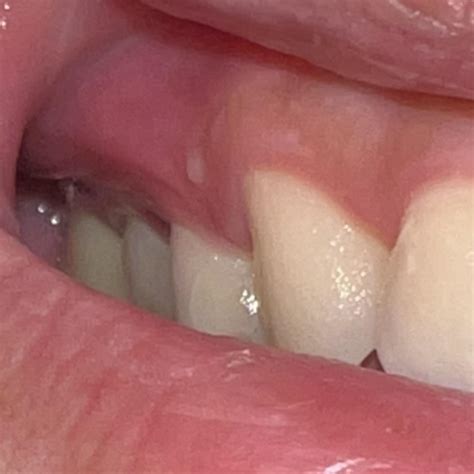

Identifying Painless Bumps on Gums

Identifying the cause of a painless bump on gums can be challenging without professional help. However, there are some steps you can take to gather more information before visiting a dentist or healthcare provider.

Visual Inspection

Carefully examine the bump for any changes in color, size, or shape. Note any accompanying symptoms, such as redness, swelling, or discharge. Take photos if possible, as this can help your dentist or healthcare provider make a more accurate diagnosis.